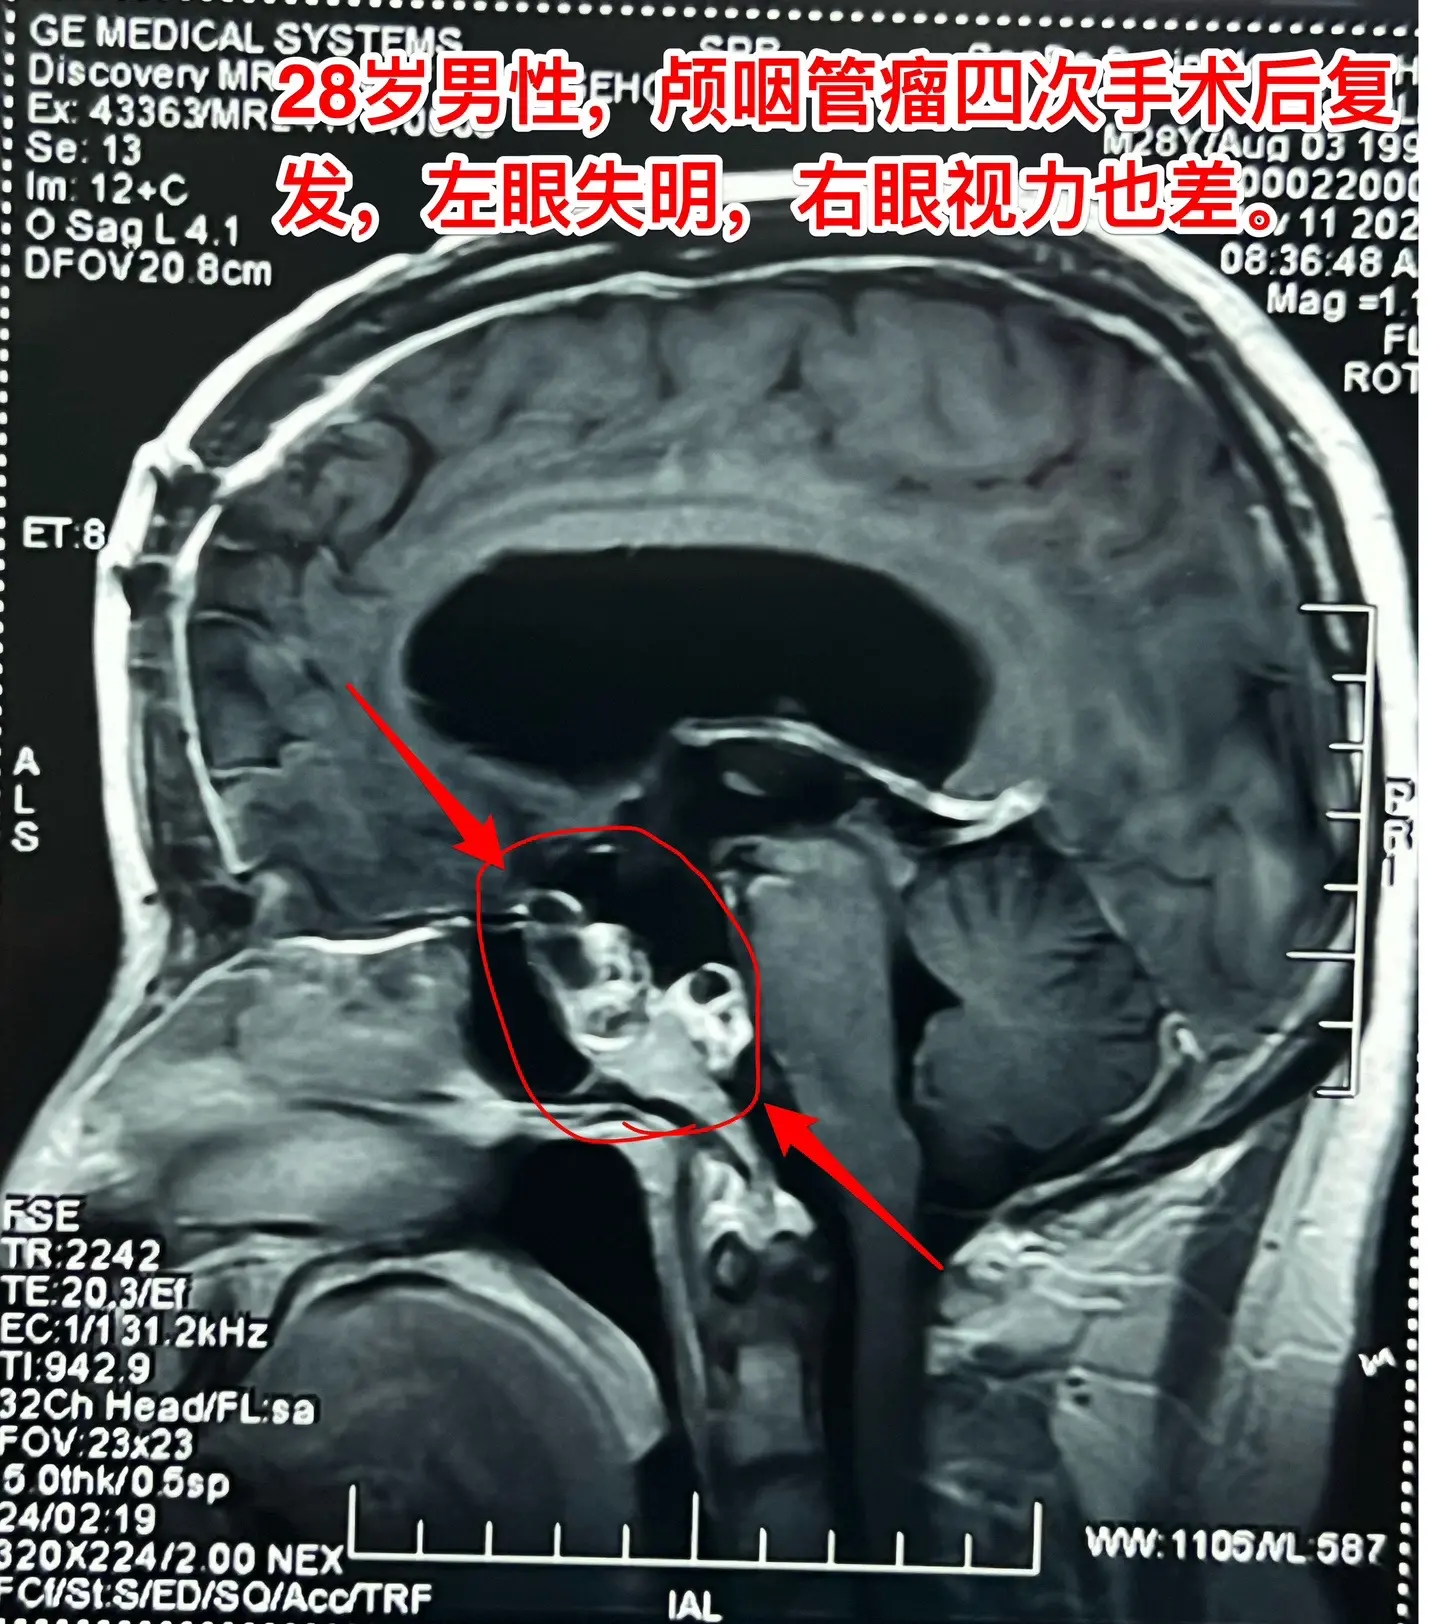

颅咽管瘤四次复发,为挽救视力只能作手术。28岁的四川小伙子,因颅咽管瘤...